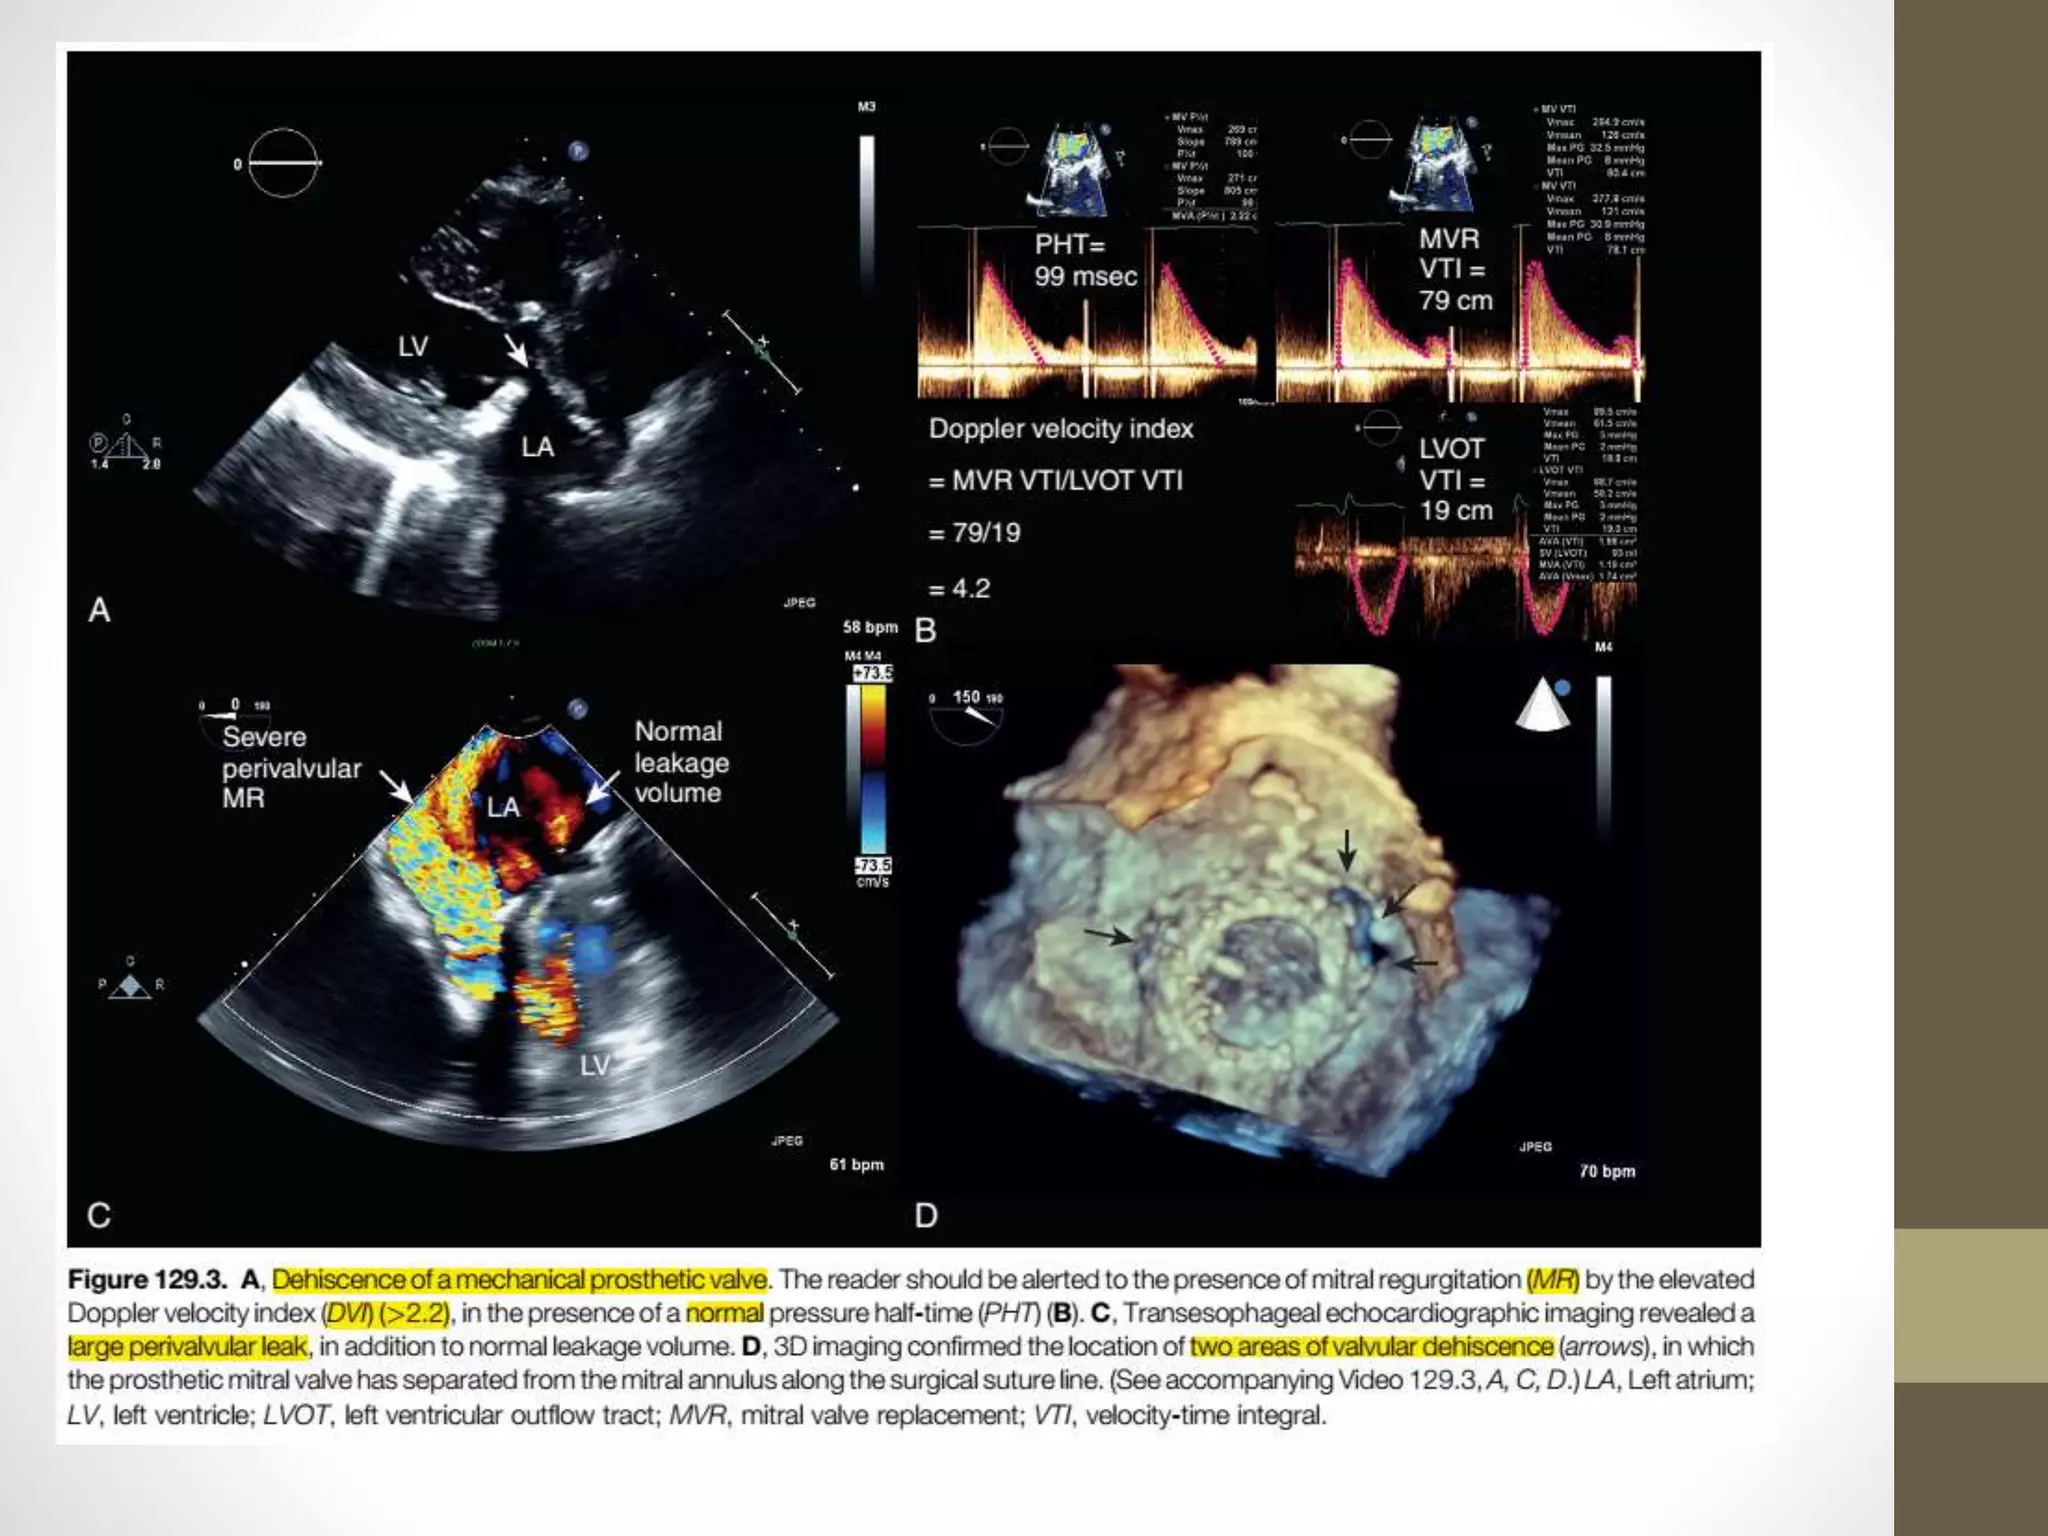

Doppler velocity index (DVI)

• a comparison of VTIPrV to VTI in the LV outflow tract

(VTILVOT)

• For prosthetic aortic valves, it is derived as VTILVOT/VTIPrV

• DVI as calculated for aortic valves is always less than unity

because velocity will always accelerate through the prosthesis;

it is normally greater than 0.25.

• prosthetic mitral valves, DVI is proposed as the inverse of that

in the aortic position: VTIPrV/VTILVOT.

• It is normally less than 2.2 for mechanical prostheses.

Pathologic Regurgitation

• Abnormal regurgitation of prosthetic valves may arise from valvular

and/or perivalvular sites.

• signs include (1) an elevated DVI, (2) elevated mitral E velocity (>1.9

m/sec), (3) a dense continuous wave regurgitant jet with early

systolic peaking, (4) a large zone of systolic flow convergence on the

left ventricular side of the prosthesis, and (5) elevated estimated

pulmonary artery pressure.

• As the DVI is elevated both by prosthetic valve obstruction (as

discussed earlier) and by regurgitation, a normal PHT (<130 msec) in

the presence of an elevated DVI (>2.2)

• strongly suggests the presence of hemodynamically significant

regurgitation, with a predictive accuracy greater than 80%,